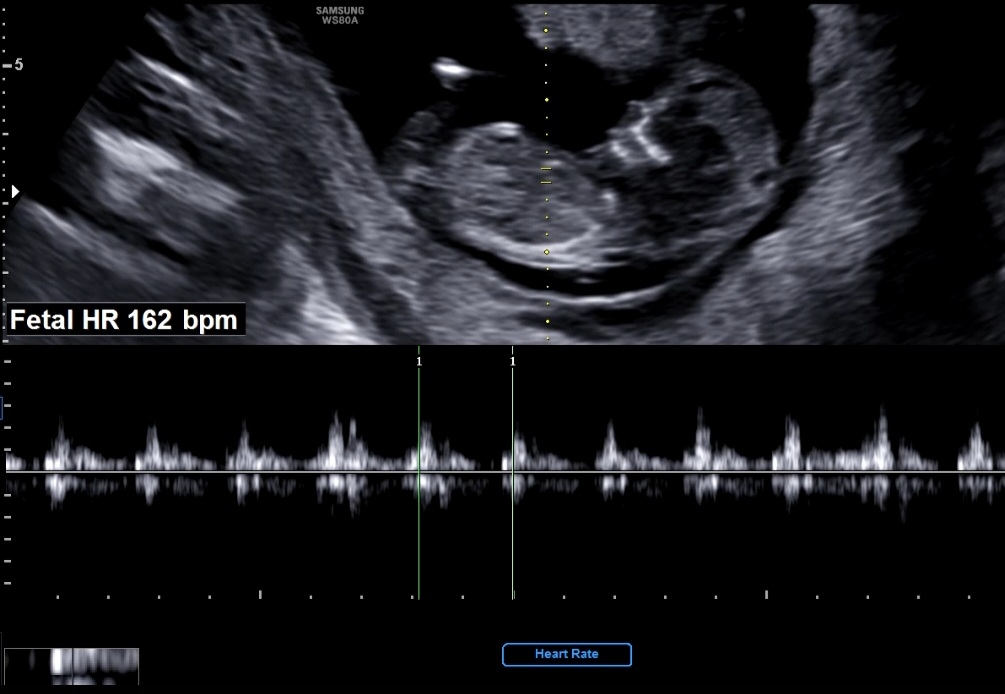

12주 초음파 각도법 봐주세요🥹

각도법 잘 보시는 분들 부탁드려요ㅎㅎ!!